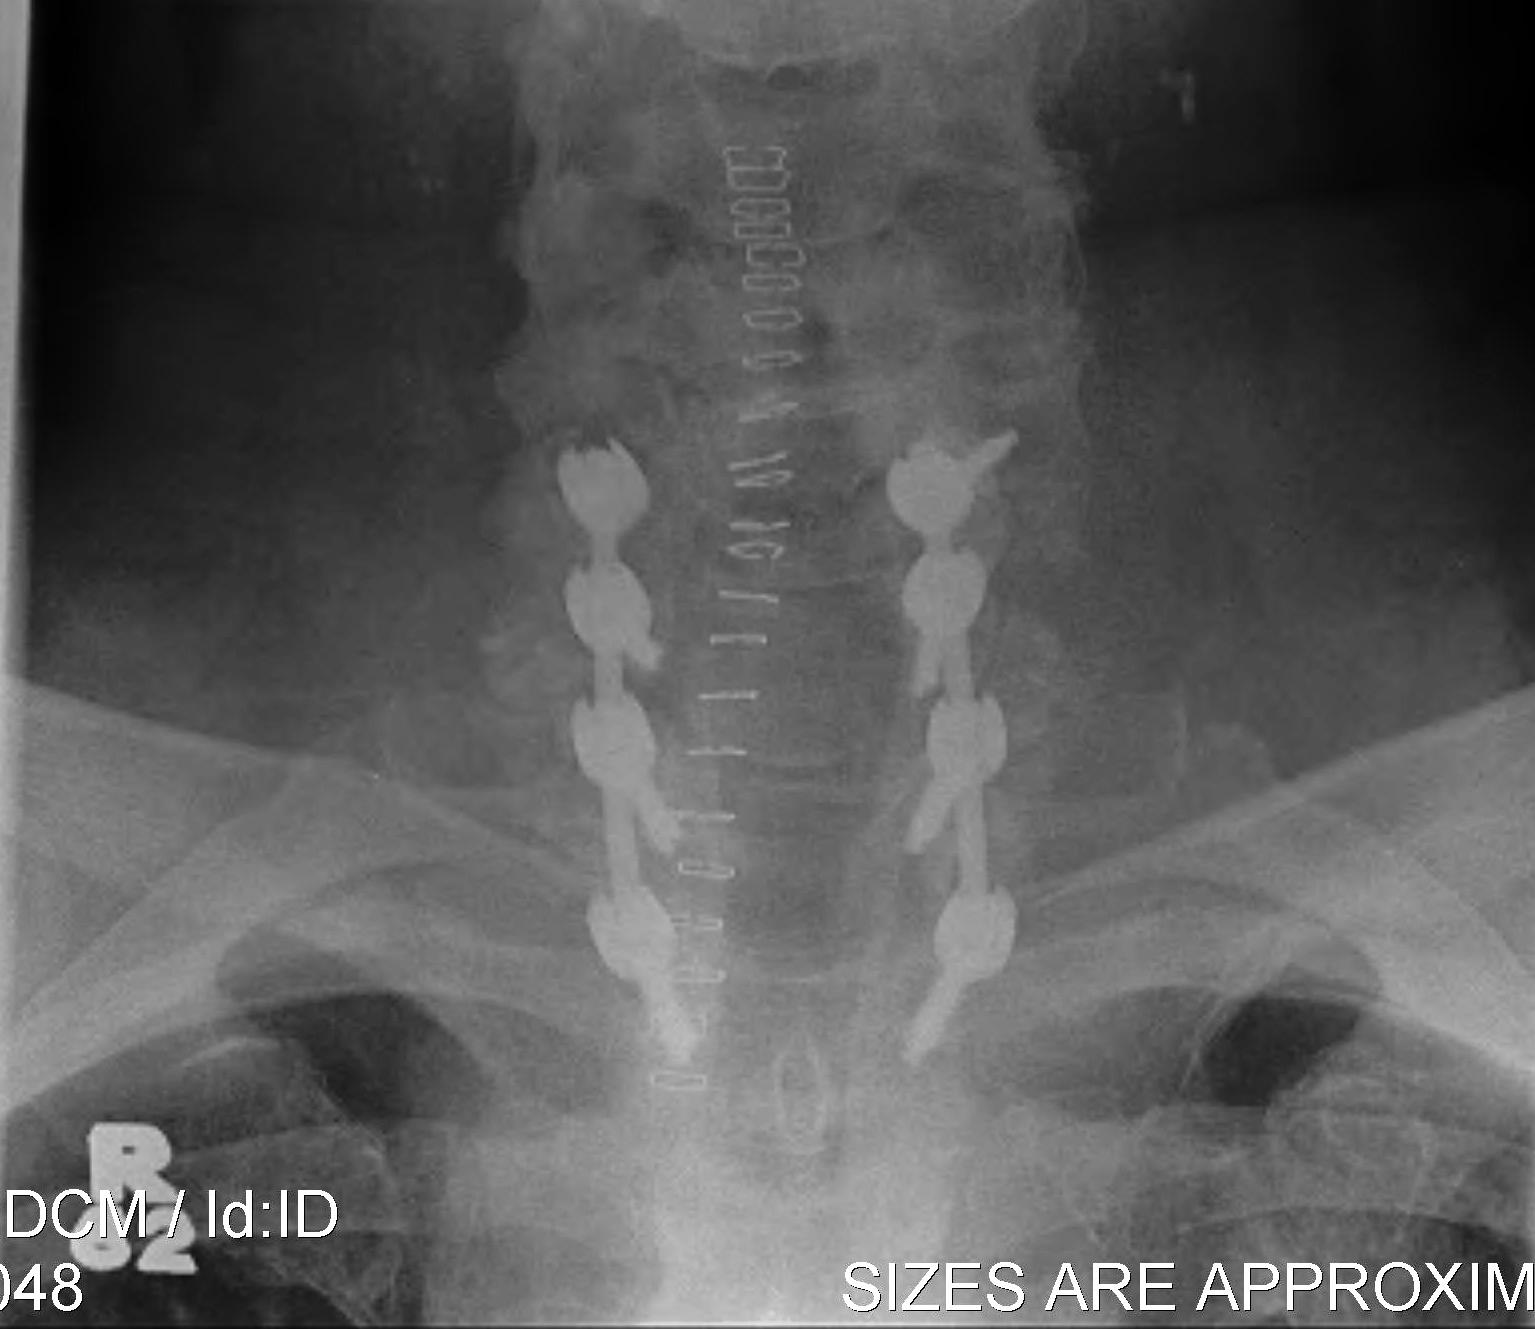

Occipito-cervical fusion

Basilar invagination / Vertical subluxation

Management

Algorithm

1. No symptoms & no cord compression on MRI - observe

2. Cord compression

- occiput to C2 fusion

- +/- C1 laminectomy

- +/- odontoidectomy